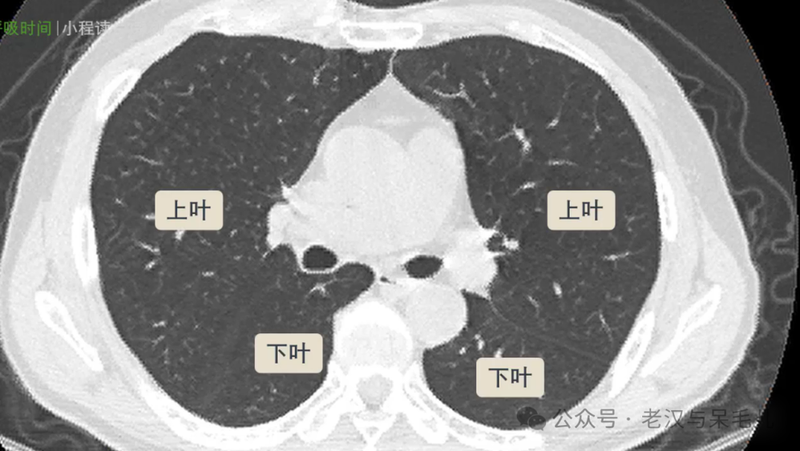

无论是左肺还是右肺,斜裂的走形都是从后上到前下,在CT横断面上表现为越靠上的斜裂越靠近后背部,越靠下的斜裂就越靠近前胸部。

左肺被斜裂分为上、下两叶,右肺被斜裂和水平裂分为上中下三叶

图片

中叶和左肺舌段水平刚好是心脏所在水平